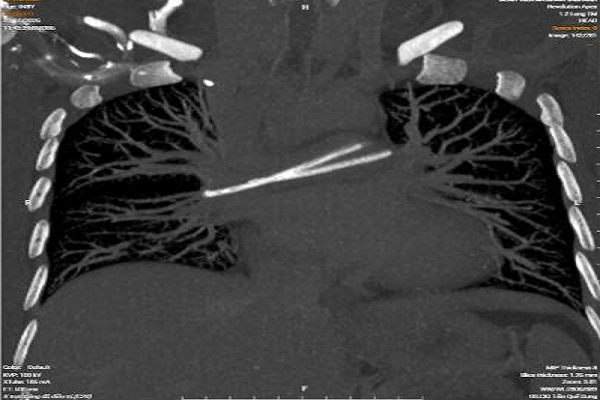

Kết quả CT cho thấy, một dị vật dài nằm vắt ngang vùng tim – động mạch phổi được xác định là một đoạn catheter - Ảnh: BVCC

Biến cố chỉ được phát hiện tình cờ trong một lần khám tầm soát định kỳ tại một cơ sở y tế tư nhân. Kết quả chụp CT ngực có tiêm thuốc cản quang khiến cả bệnh nhân lẫn bác sĩ đều bất ngờ: một dị vật dài nằm vắt ngang vùng tim – động mạch phổi, hình ảnh điển hình của một đoạn catheter đã bị đứt và trôi sâu vào hệ tuần hoàn.

Sau khi quay lại bệnh viện công nơi từng điều trị ung thư, bệnh nhân được chụp X-quang ngực. Kết quả xác nhận nghi ngờ ban đầu: thân catheter đã mất tính liên tục. Phần buồng truyền vẫn nằm dưới da vùng dưới xương đòn phải, trong khi đoạn đầu còn lại đã di chuyển theo dòng máu về tim và mắc kẹt tại vị trí chia nhánh của động mạch phổi hai bên.